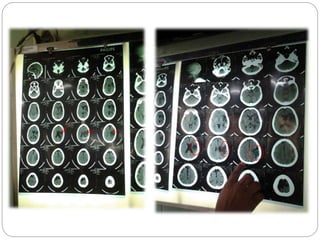

 Por imágenes.- El mas esencial es elTC, donde nos muestra

 Tomografía computarizada: crecimiento secuencial de

izquierdos (día +1 [A], +2 [B] y +5 [C])

TOMOGRAFIA COMPUTARIZADA DE CEREBRO